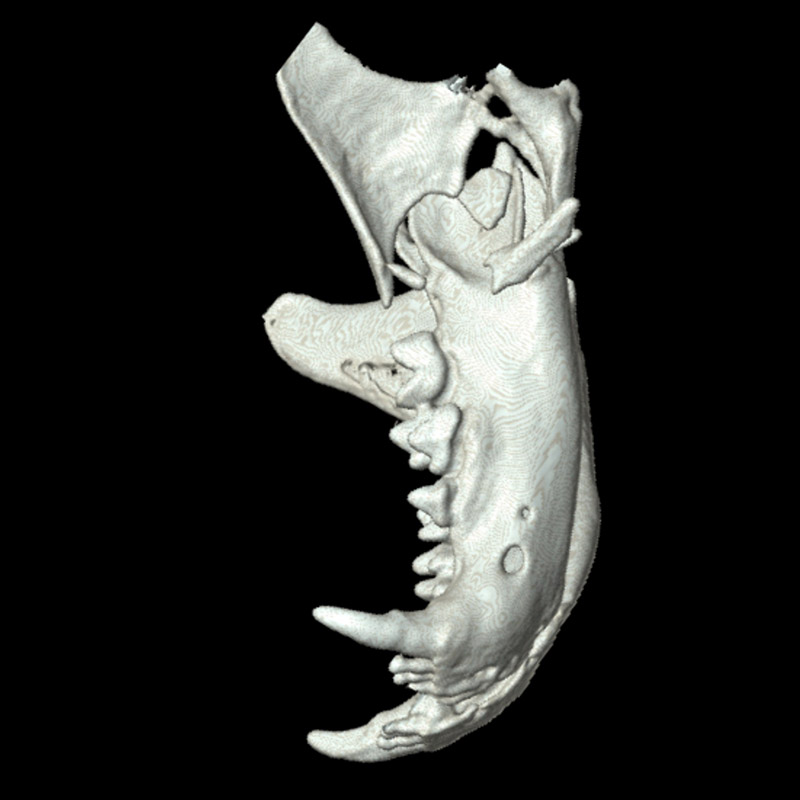

下顎骨骨折

雑種猫(14歳)

犬に咬まれた

手術前

手術後

CT横